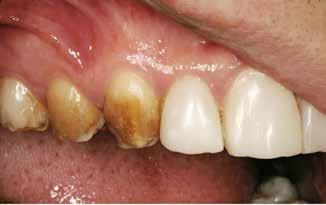

En 40 år gammel mand henvendte sig med bekymring for både æstetik og symptomer fra tænderne (Fig. 1). Han fortalte, at

Fig. 1. 40-årig sund og rask mand møder bekymret for sine slidte tænder. Klinisk ses frakturer og substanstab langs incisalkanterne på overkæbetænderne.

Fig. 1. A 40-year-old healthy man is concerned for his worn teeth. Clinically, fractures and loss of tooth substance are observed at the incisal edge of the upper front teeth.

han de seneste år havde mærket, at tænderne var blevet kortere og mere takkede, og han mærkede isninger ved indtagelse af kolde drikke. Han oplyste, at han i mange år havde drukket coca-cola dagligt, og at han skar tænder. Ellers var han sund og rask, og han havde normal salivaproduktion.

Klinisk undersøgelse viste et tandsæt med enkelte restaureringer, men med slitagedefekter okklusalt/incisalt på samtlige tænder fra 6’er til 6’er i over- og underkæbe (Fig. 2). Defekterne strakte sig tydeligt ind i dentinen. Baseret på anamnesen og de kliniske fund blev erosion set som hovedårsagen til tandsliddet, mens attrition formodedes at være en medvirkende faktor.